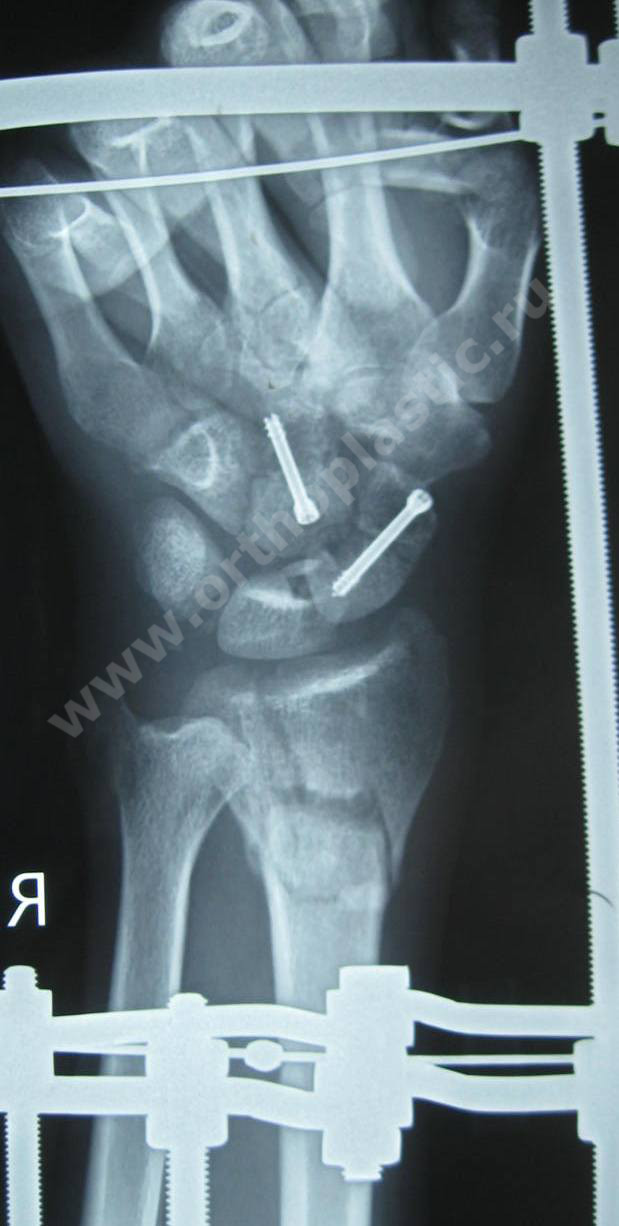

1- рентгенограмма пациента К. с переломом ладьевидной кости, переломом головчатой кости, перелом дистального метаэпифиза лучевой кости

2- рентгеграмма пациента К. после открытой репоцизии, остесинтеза костей запястья компрессирующими винтами